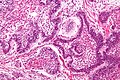

Ameloblastoma. H&E stain. | |

| LM | stellate reticulum (star-shaped cells), tall columnar cells that have palisaded nuclei with reverse polarization, subnuclear vacuolization, +/-giant cells, +/-subepithelial hyalinization (eosinophilic acellular amorphous material) |

Features:[7]

- Stellate reticulum - star-shaped cells, found in a developing tooth.

- Tall columnar cells.

- Palisaded nuclei with reverse polarization.

- Reverse polarization of nuclei = nuclei distant from the basement membrane/nuclei at pole opposite of basement membrane.

- Palisaded nuclei = picket fence appearance; columnar-shaped nuclei with long axis perpendicular to the basement membrane -- key feature.

- Subnuclear vacuolization.

- +/-Giant cells.

- +/-Subepithelial hyalinization (eosinophilic acellular amorphous material).

- Seen deep to the basement membrane.

- Variable morphology (see below - morphology).